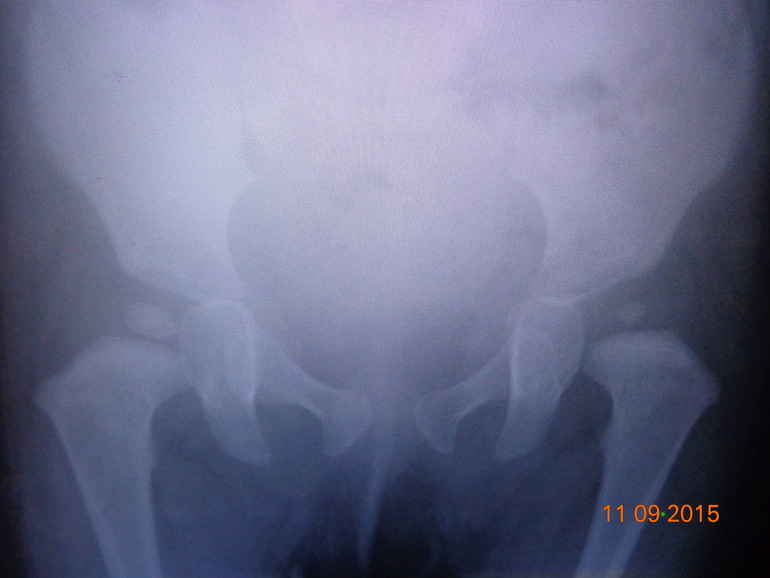

Наталья 10 лет Можно снять шину?? Ваше мнение????? дисплазия Всем привет!!Сделали снимок, в теории должны закончить лечение! Как думаете, разрешат снять шину Виленского??? Лечимся 8 мес, ребенку 1г 2мес. После предыдущего снимка, проблемы оставались только слева. Ваше мнение??? Посмотрите еще 20 записей на эту тему Отменить Ответить Чаты Беременных Выберите чат: Январята-2026 Февралята-2026 Мартята-2026 Апрелята-2026 Майчата-2026 Июнята-2026 Июлята-2026 Августята-2026